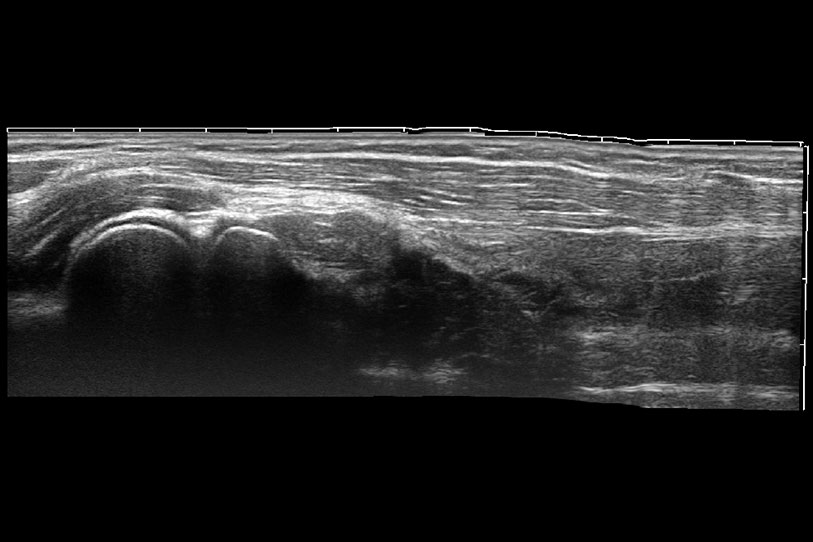

通過色彩血流和實(shí)時寬景相結(jié)合,可觀察到完整的靜脈或動脈的血流,方便醫(yī)生檢查。實(shí)時掃查過程中,如有任何操作失誤也可以很容易地進(jìn)行回掃擦除,而不會中斷掃查。